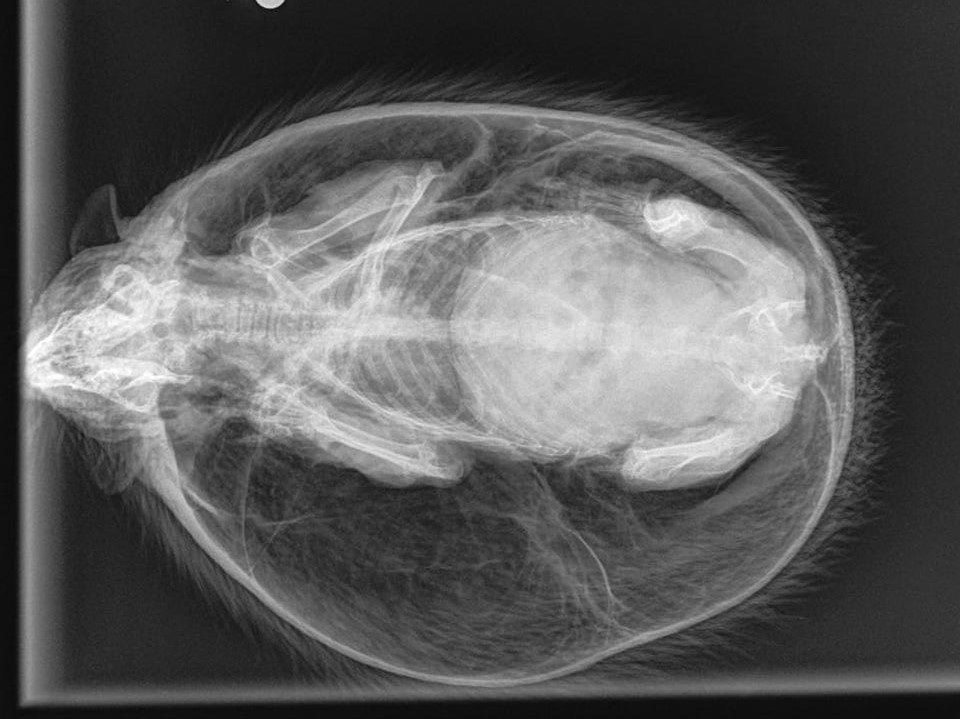

Ảnh chụp X quang con nhím

"Con nhím này phình to gần gấp đôi kích cỡ tự nhiên của nó, nở phồng như một quả bóng bãi biển. Tôi đưa con vật đến Sheffield, nơi nó được chụp X quang và thả một ít không khí ra khỏi cơ thể”.